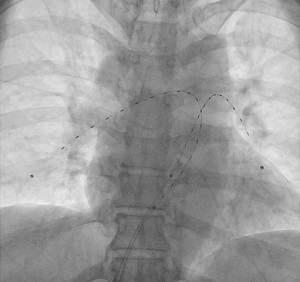

EKOS catheter thrombolysis for pulmonary embolism

One type of catheter directed thrombolysis for pulmonary embolism is with the EKOS catheter. The EKOS catheter delivers thrombolytic agents into the clot in a unique fashion. The catheter has ultrasound ports near its tip. Ultrasound energy is used to spray the thrombolytic agent into the clot. The EKOS catheter is inserted into the pulmonary embolism. It is left there for several hours while thrombolysis is taking place. Typically tPA is used. It is dripped at a pace of 1 mg/hour for several hours and then the rate is reduced to 0.5 mg/hour for several hours more. Heparin is given in tandem, mainly to prevent catheter thrombosis.